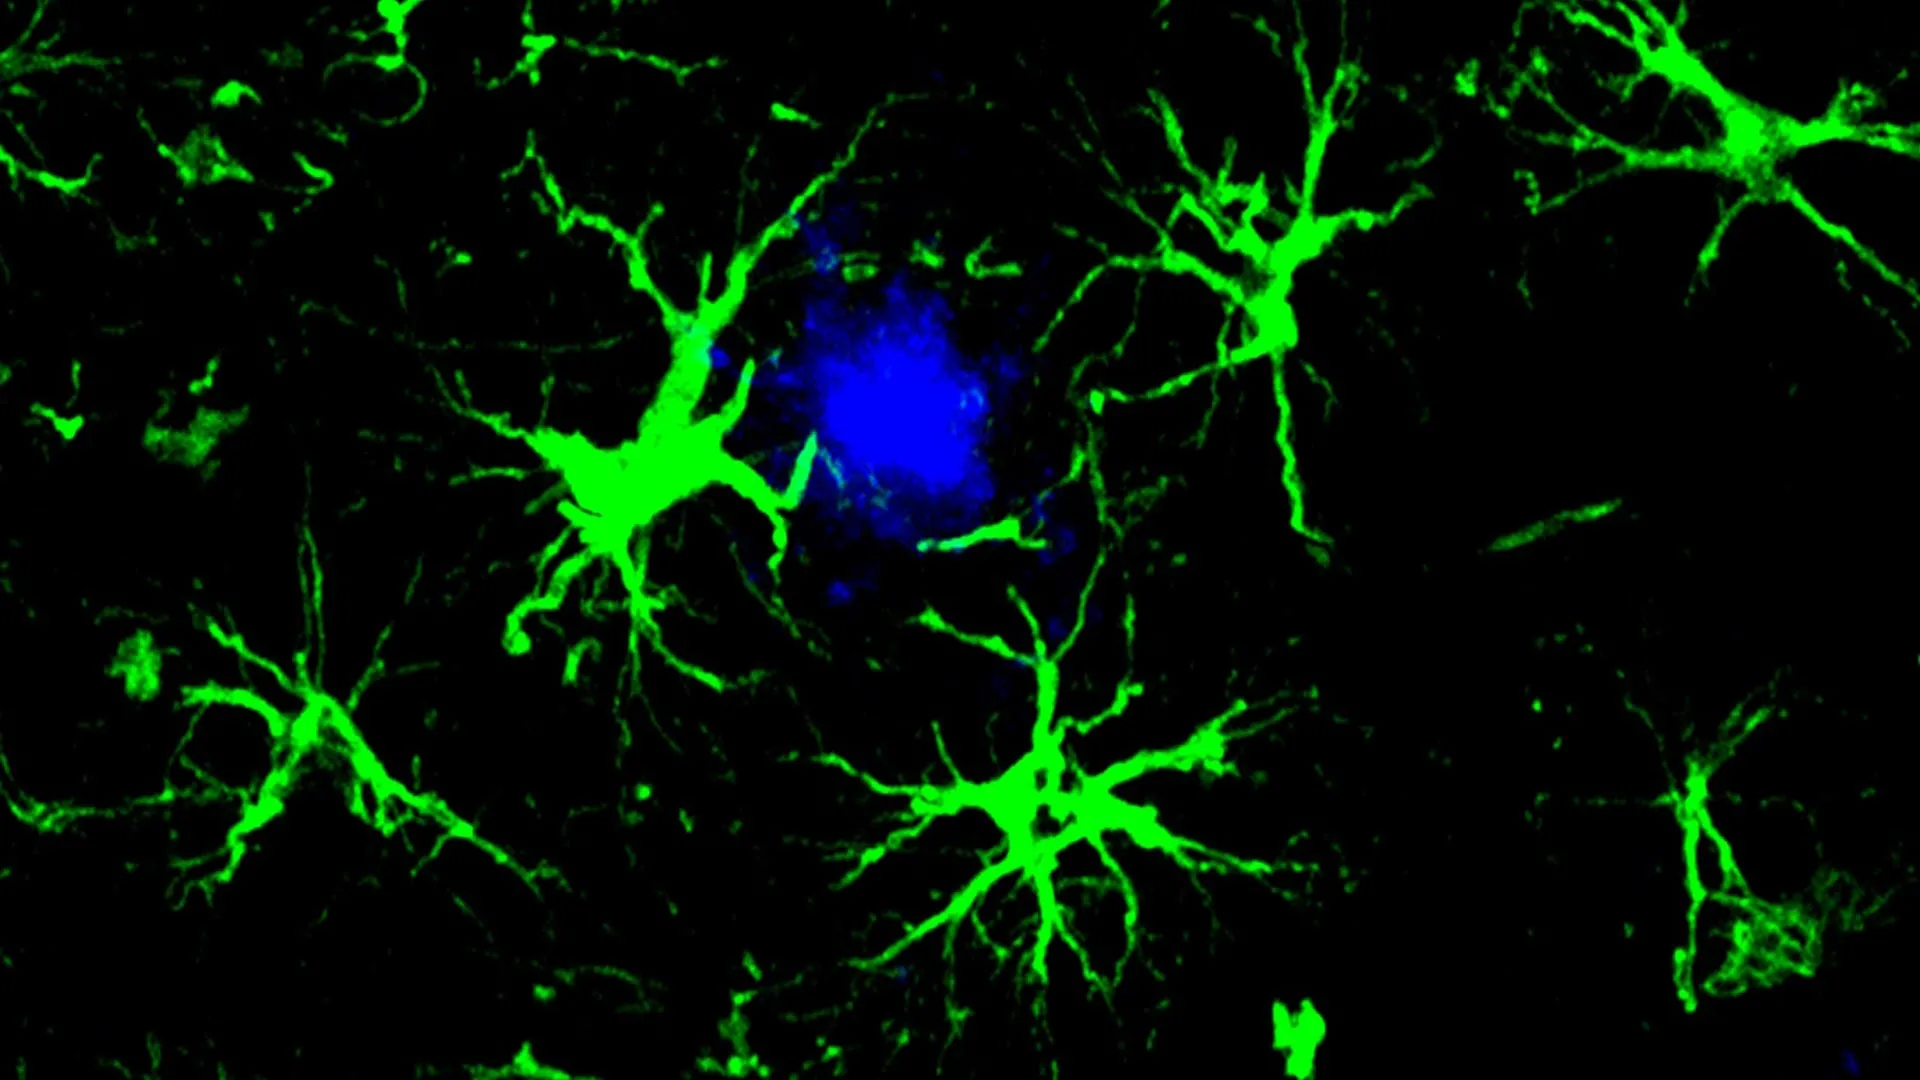

These engineered CAR-astrocytes act like powerful cleaning cells in the brain. Their design allows them to locate and remove harmful proteins that contribute to cognitive decline.

To reduce the burden on microglia, first author Yun Chen, PhD, then a graduate student working in the laboratories of Colonna and David M. Holtzman, MD, the Barbara Burton and Reuben M. Morriss III Distinguished Professor of Neurology at WashU Medicine, focused on astrocytes. Astrocytes are the most abundant cells in the brain and typically help maintain a healthy environment for neurons.

Chen redesigned astrocytes to become specialized amyloid clearing cells. He introduced a gene that produces a chimeric antigen receptor (CAR) into astrocytes using a harmless virus injected into mice. Once expressed on the surface of the astrocytes, the CAR allowed the cells to capture and swallow amyloid beta proteins. With this added ability, the astrocytes concentrated on removing amyloid beta plaques in mice that are prone to developing them. Astrocytes normally help maintain order in the brain.